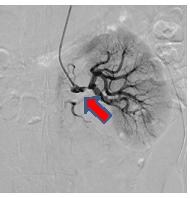

経皮的冠動脈インターベンションの一例

- 【1】術前

-

- 【2】ワイヤー通過

- 【3】ステント留置

- 【4】術後